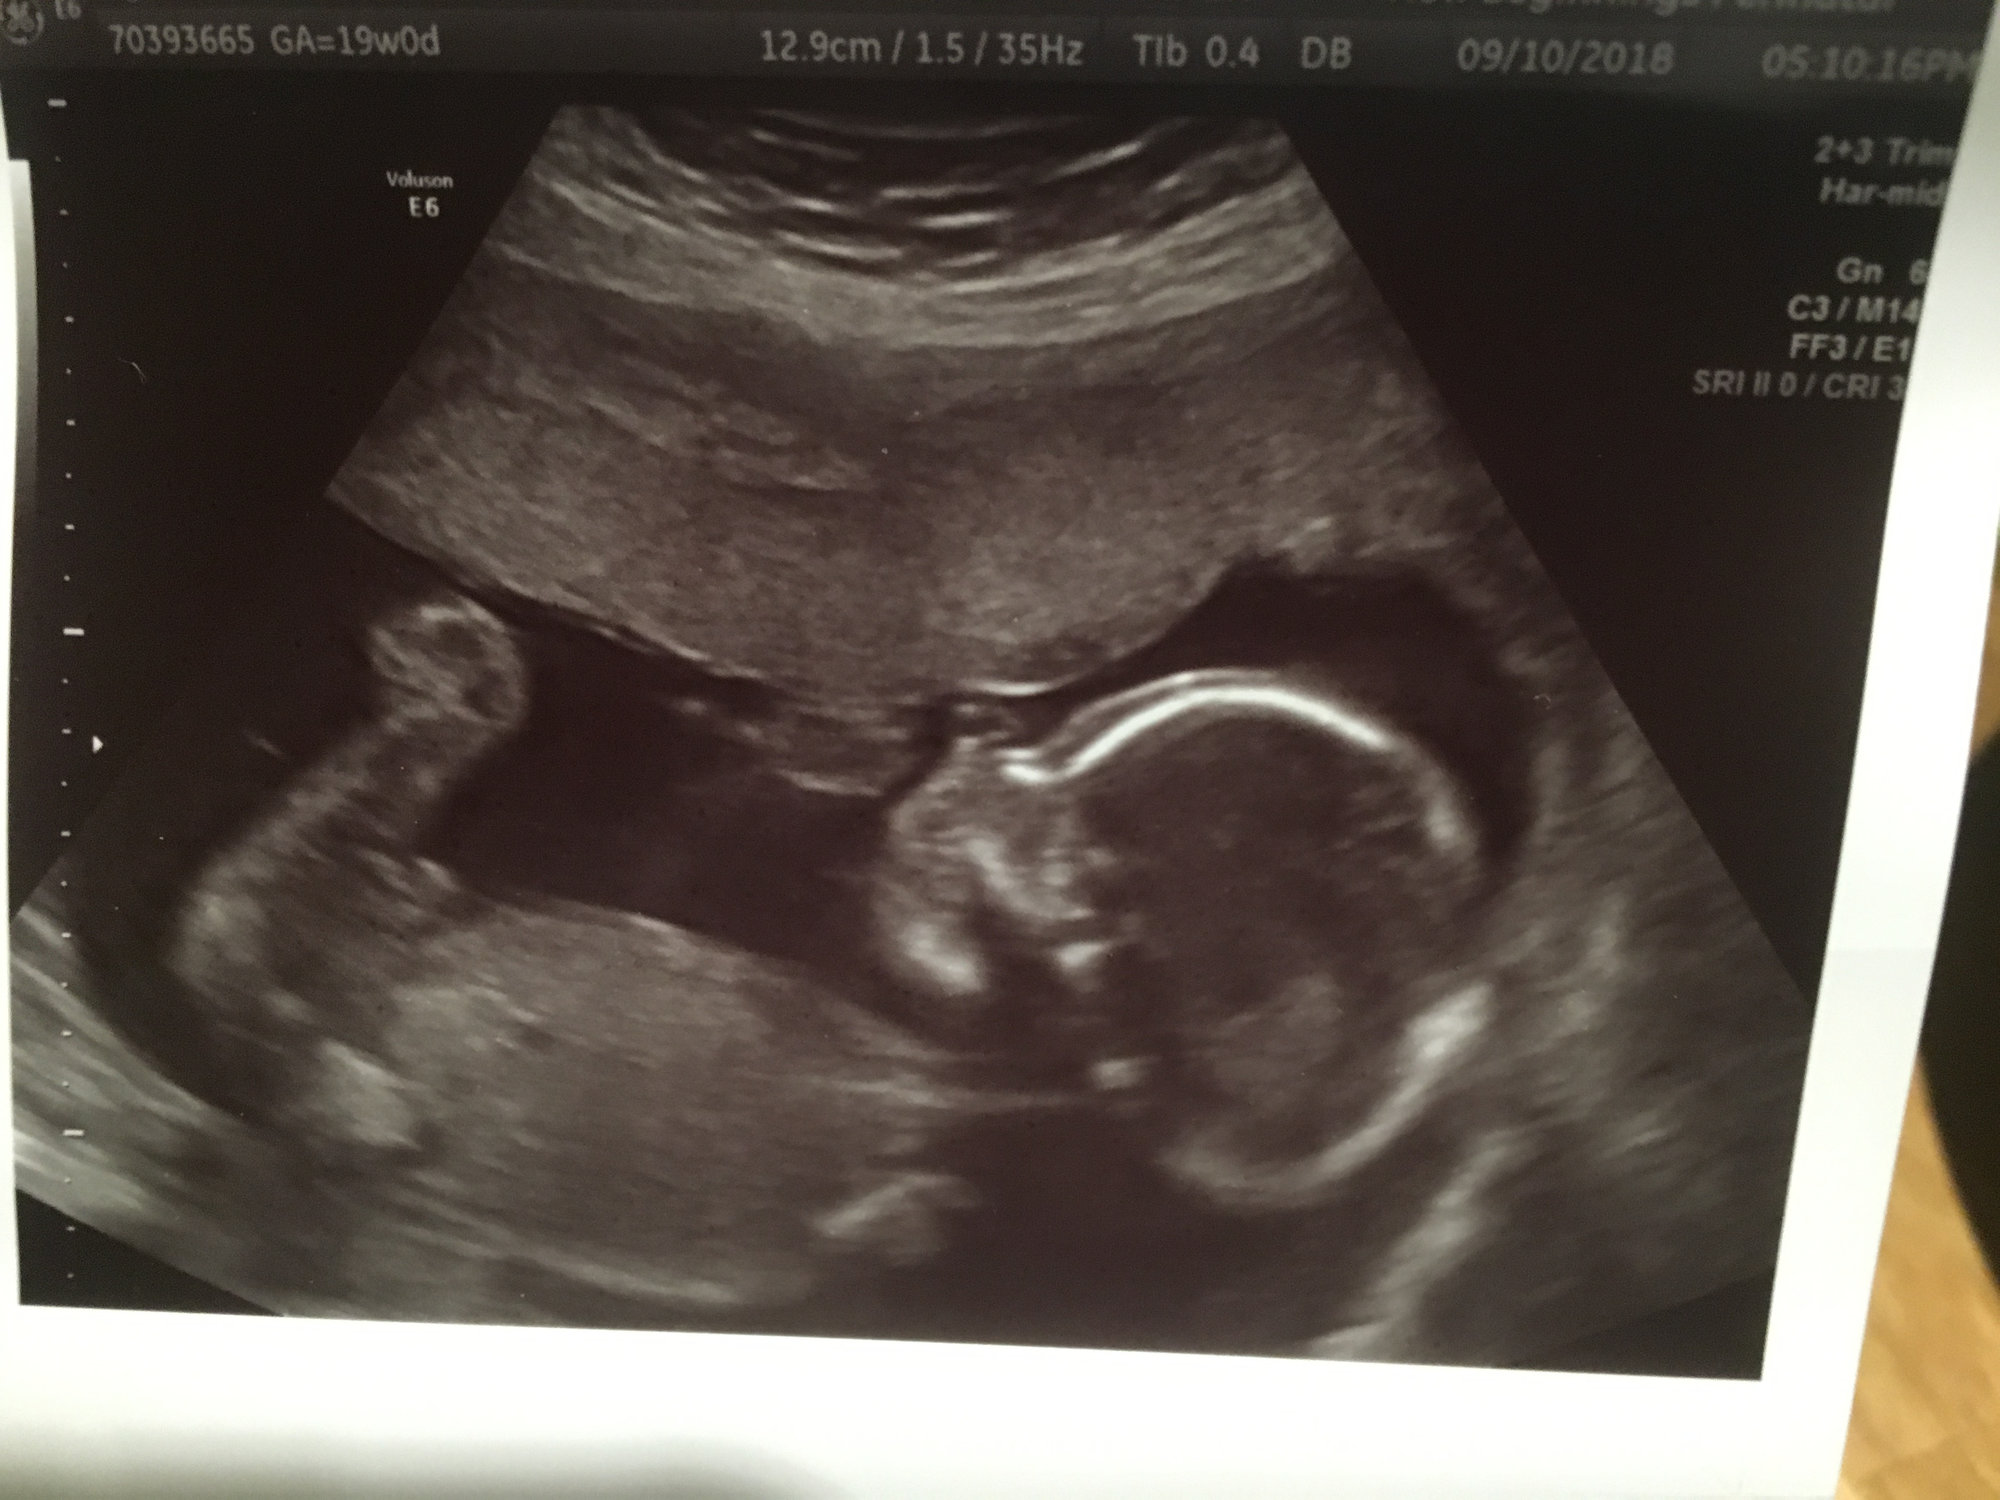

How far along? 19 weeks - I’ve got a zucchini in here!

Appts this coming week? AS today and monthly Doppler appt Thursday

my AS went well! My tech wouldn’t say anything (boo) but I talked to the dr after and he said everything appeared normal/healthy. My placenta is anterior which explains why I only feel movement down low and on the sides. Baby was facing my back and the cord was across his face so the pics kind of sucked but we got a couple of nice ones. He weighs 9oz which seems to be right on track as well. I go back on 10/4 for an echocardiogram.